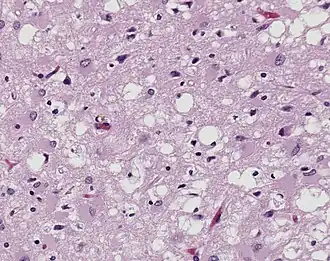

%252C_H%2526E.jpg)

Exposure to animal with diseases are a risk for agricultural workers. Zoonosis are diseases that are transmitted from infected animals to humans. Most zoonotic diseases are caused by organisms such as parasites, bacteria, prions, fungi, protozoa, and viruses, which reside within the animal but can be pathogens to humans. Direct or indirect transmission from feces or bodily fluids can result in infection, and consuming animal products that are contaminated can also become a cause of infection.[17] Because of their close contact with animals, farmers, veterinarians, ranchers, and other agricultural workers are more at risk for contracting zoonotic diseases.

Examples of zoonotic diseases include anthrax, avian influenza, brucellosis, cryptosporidiosis, giardiasis, leptospirosis, mycobacterium bovis, orthohantavirus, psittacosis, rabies, tularemia, and Zika virus.